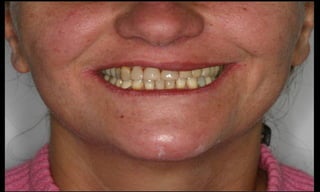

Baixo potencial para perda óssea marginal

(Tenenbaum et al. Impl Dent, 2003);

Resultados estéticos periimplantares otimizados

(Abboud, M. IJOMI, 2005).